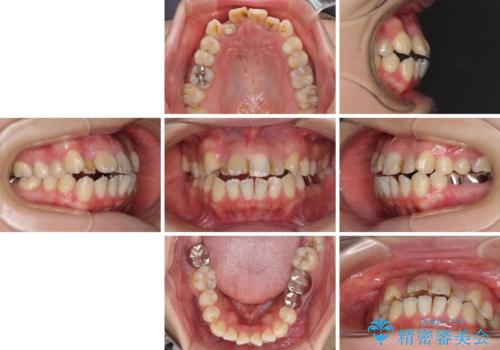

- 八重歯と前歯のデコボコ、開咬を気にして来院された患者様です。

抜歯矯正が必要であることはご自身で理解されており、目立たない装置をご希望であったので、上顎が裏側装置であるハーフリンガル装置にて治療を行うこととしました。

上顎前歯や下顎大臼歯に根管治療の必要な歯がいくつかあるため、矯正治療と並行して根管治療を行い、その後オールセラミッククラウンにて補綴治療を行うこととしました。